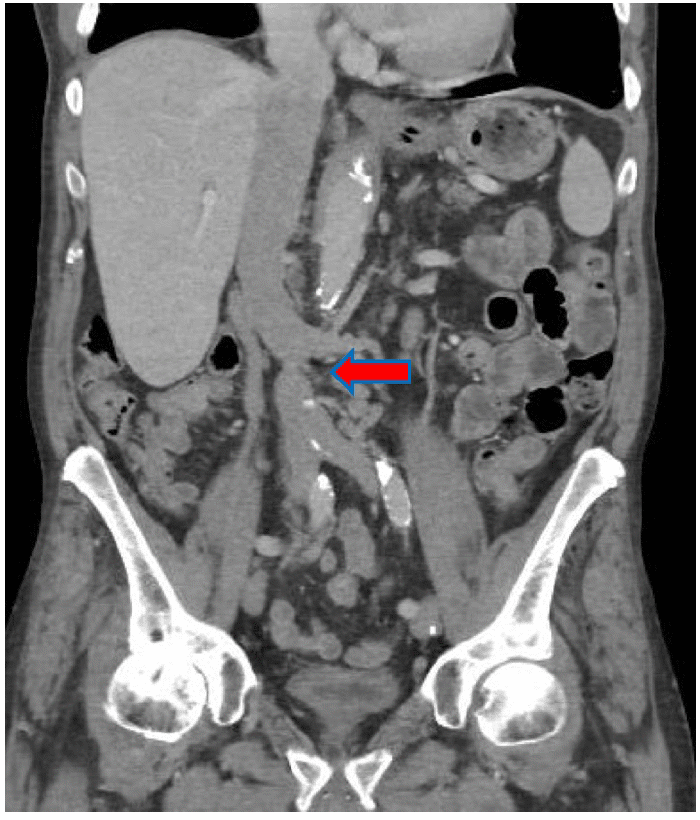

An end-to-side anastomosis between the inverted donor IVC and recipient IVC was created above the obstruction and below the native renal veins, and an end-to-side anastomosis between the donor renal artery and recipient external iliac artery was created (Figure 3). A Lich ureterocystostomy was then performed.

Figure 3. Intraoperative Photo. Published with Permission

End-to-side donor renal vein to donor IVC conduit anastomosis (arrow). End-to-side donor IVC to recipient IVC anastomosis (arrowhead). Conventional end-to-side donor renal artery to recipient external iliac anastomosis (star)